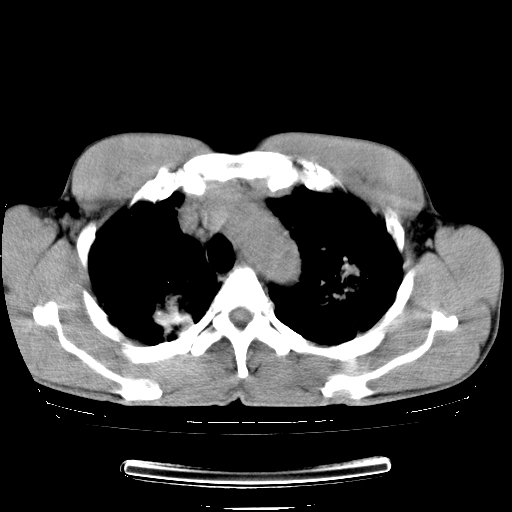

以下是引用yangyudong333在2008-4-29 5:38:00的发言:[br]比较典型的矽肺结节.支持[br]诊断依据:[br] 1.x线表现:[br] ①典型矽肺为多发直径 1~3mm 小结节,即矽结节,由胶原纤维和硅尘构成,可融合成团块,好发于上肺。[br] ②团块周围常有肺大泡。[br] ③胸内淋巴结增大、钙化。如肺门淋巴结呈蛋壳样钙化有助于与其他尘肺区别。[br] ④胸膜常广泛粘连、增厚。[br] 2.ct表现[br] ①两肺散在大小较为一致的小结节影,其密度较高,边界清楚。[br] ②小结节可融合为较大团块影,直径约 1cm ,甚至可达 10cm以上,易发生在上叶。[br] ③小结节周围常并有小叶中心气肿或弥漫性肺气肿。

以下是引用liuyue在2008-4-28 22:30:00的发言:[br]比较典型的矽肺结节.[br]请结合临床及化验除外矽肺合并肺结核之可能.